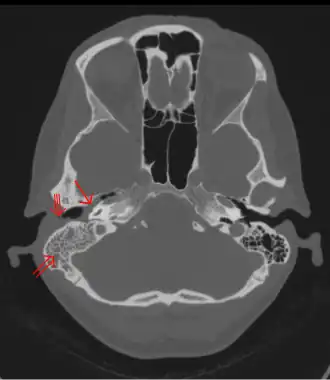

Photographie d'une mastoïdite, inflammation de la mastoïde.

Une mastoïdite est une inflammation de la mastoïde. Il s'agit d'une forme de complication de l'otite, pouvant survenir en raison de la communication entre les cavités de l'oreille moyenne et celles de la mastoïde.